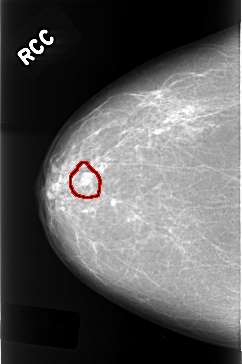

C_0319_1.RIGHT_CC

FILE: C_0319_1.RIGHT_CC.OVERLAY

TOTAL_ABNORMALITIES 1

ABNORMALITY 1

LESION_TYPE MASS SHAPE LOBULATED MARGINS CIRCUMSCRIBED

ASSESSMENT 3

SUBTLETY 5

PATHOLOGY BENIGN

TOTAL_OUTLINES 1

BOUNDARY